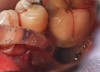

Fig 45. The definitive crown tooth No. 26 seated in place and provisionally cemented. The recession defect was eliminated with the removal and replacement of a new implant in the proper position.

Figure 45

Fig 46. The post-treatment radiograph showing a healthy stable implant and restoration.

Figure 46